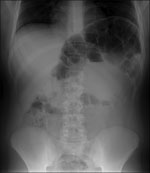

Sau khi nhập viện, cậu bé đã biểu hiện táo bón nặng và giải thích rằng cậu bé mỗi tuần chỉ đại tiện một lần. Kết quả xét nghiệm lúc nhập viện, kể cả huyết thanh natriuretic peptide não và nhìn chung các chỉ số đều trong phạm vi cho phép. Tuy nhiên khi chụp X quang ở phần bụng cho thấy sự căng phồng ở đại tràng chính và kéo dài 65 mm.